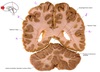

1

Q

a

body of corpus callosum

2

b

Anterior horn of lateral ventricle

3

c

Septum pellucidum

4

d

Rostrum of corpus callosum

5

e

Head of caudate nucleus

6

f

Anterior limb of internal capsule

7

g

Putamen

8

h

Nucleus accumbens